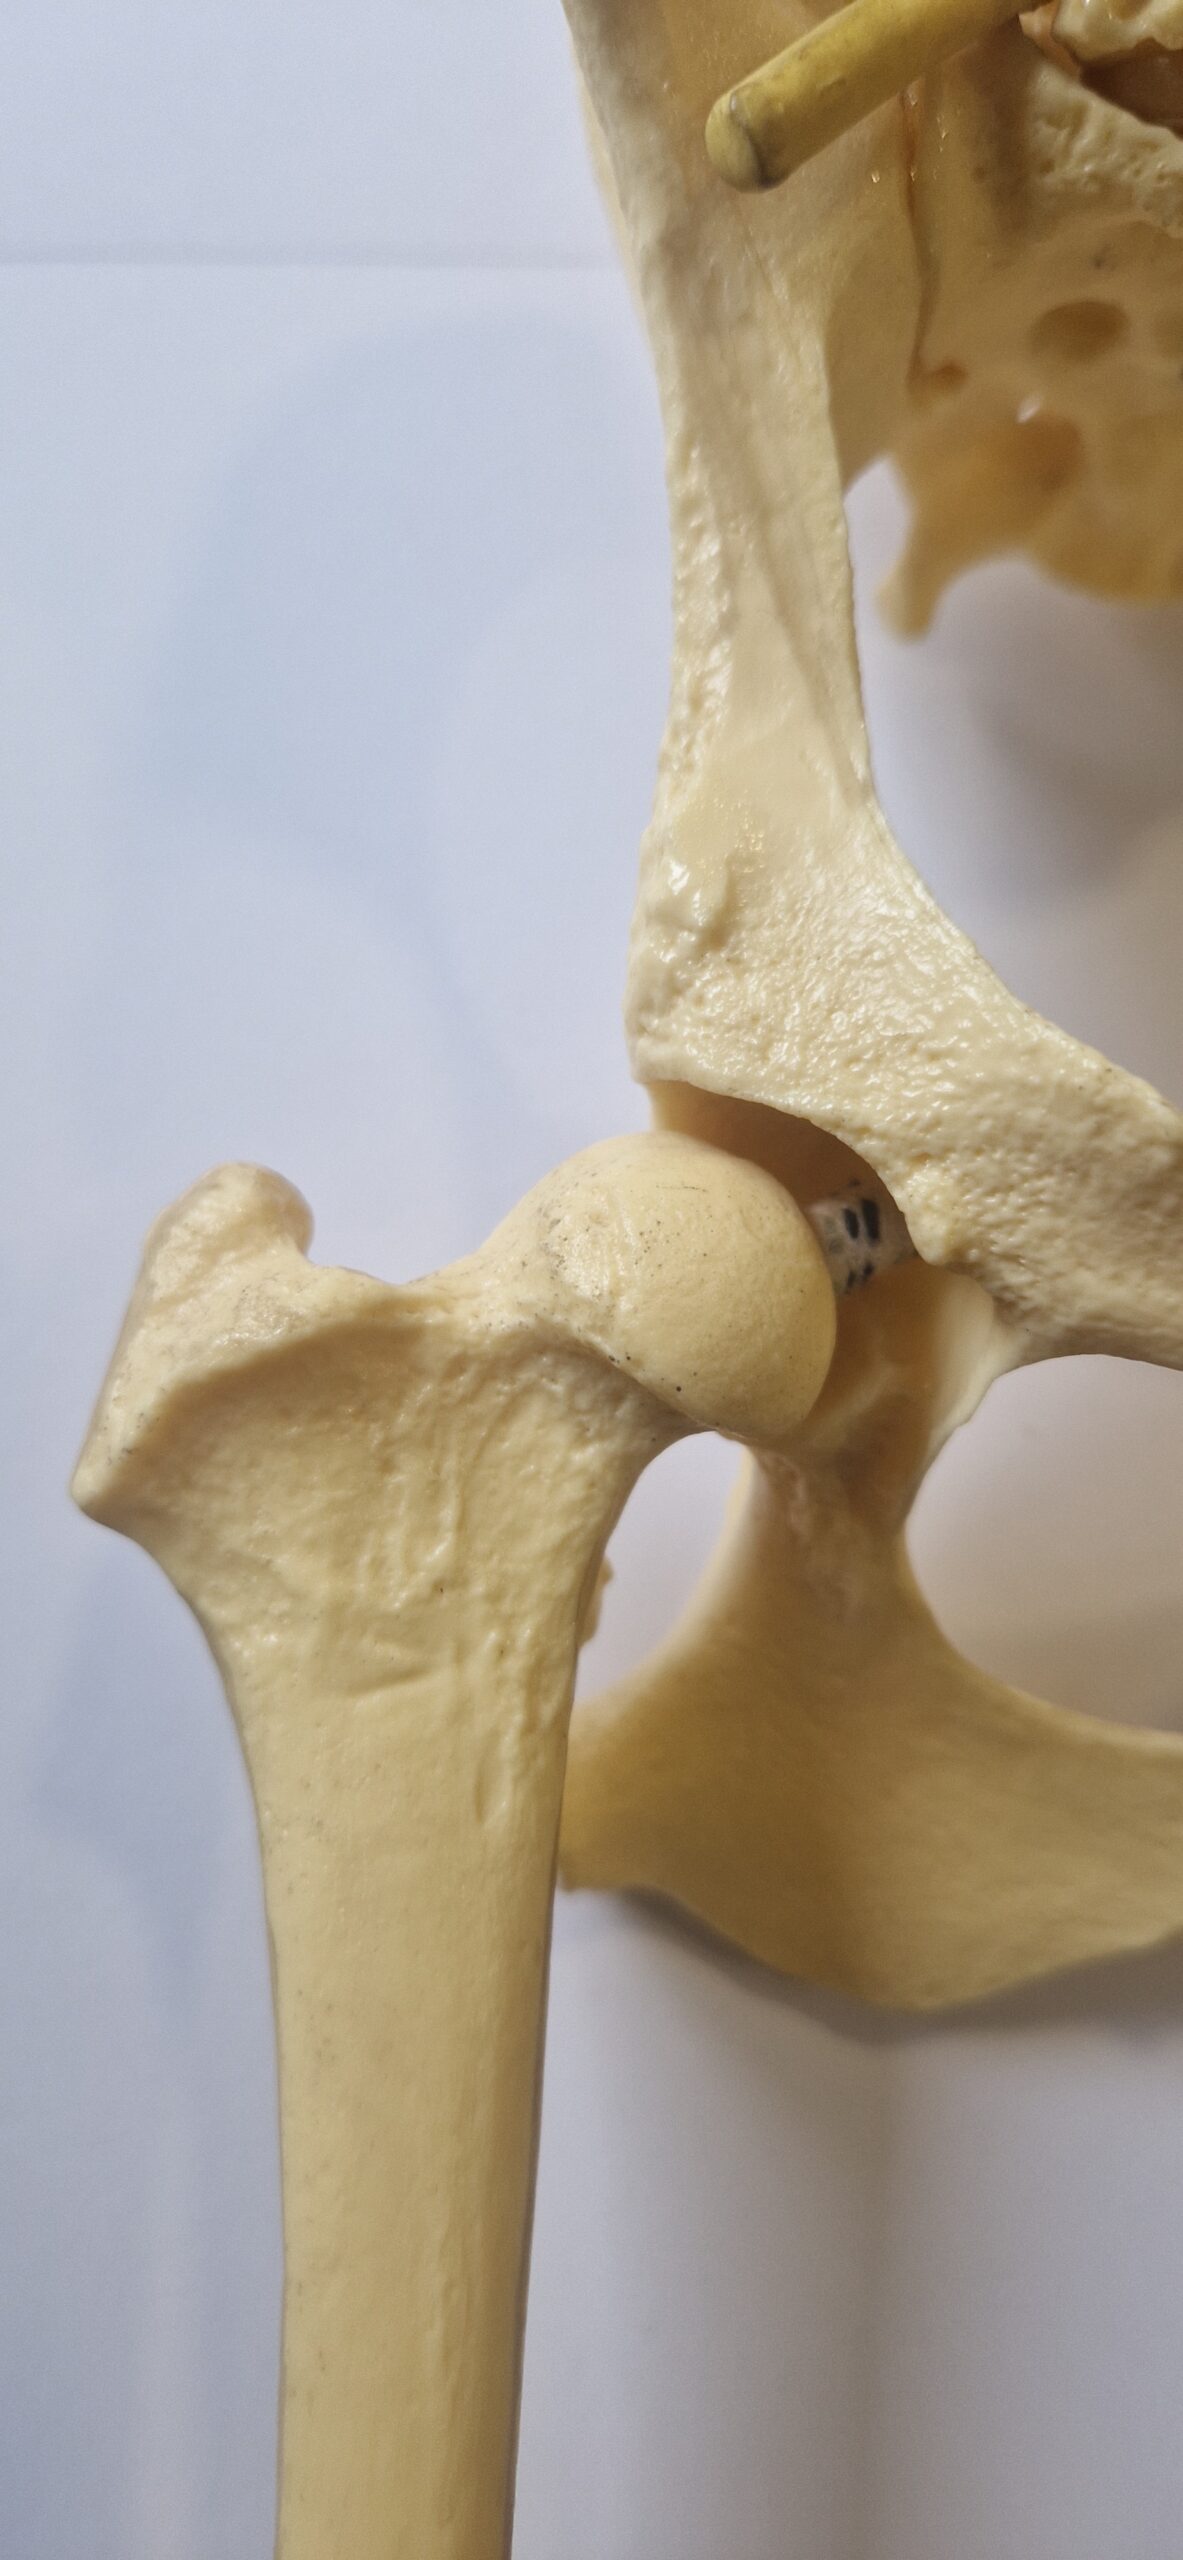

La dysplasie des hanches est une maladie articulaire. L’articulation de la hanche est formé par l’union de deux os, le bassin d’une part, et le fémur d’autre part. L’os du bassin possède deux cavités appelées « acétabulum ». Le fémur se termine en haut de la cuisse par une sphère appelée la « tête du fémur ». Dans les articulations en bonne santé, la tête de fémur va s’emboiter parfaitement dans l’acétabulum du bassin. Par contre chez certains chiens, cette emboitement n’est pas optimal! La tête du fémur est moins arrondie, la cavité du bassin moins bien creusée et recouvre moins bien la tête du fémur… il y a une instabilité plus ou moins marquée dans l’articulation.

hanche idéale

hanche légèrement instable

hanche fortement instable

Comme expliqué plus haut, l’articulation de la hanche est formée par l’union de deux os, l’acétabulum du bassin et la tête du fémur. La tête du fémur est maintenue bien enfoncée dans l’acétabulum par le ligament rond représenté par un large élastique blanc et bleu dans les images plus haut. Chez le chien dysplasique, dès l’âge de 1 mois (eh oui quand il est chiot!) ce ligament rond va prendre un aspect légèrement œdémateux et perdre quelques fibres. Cela va lui procurer une plus grande laxité et rendre l’articulation de la hanche moins stable. La tête du fémur va bouger légèrement dans la cavité acétabulaire. Il va y avoir à chaque mouvement, à chaque choc, des micros-traumatismes sur le cartilage de cette tête fémorale et de la cavité acétabulaire du bassin. Cela va conduire à un remodelage de ces 2 surfaces articulaires. La cavité sera moins creusée, la tête fémorale sera moins ronde. Ces phénomènes vont encore plus accentuer l’instabilité articulaire.